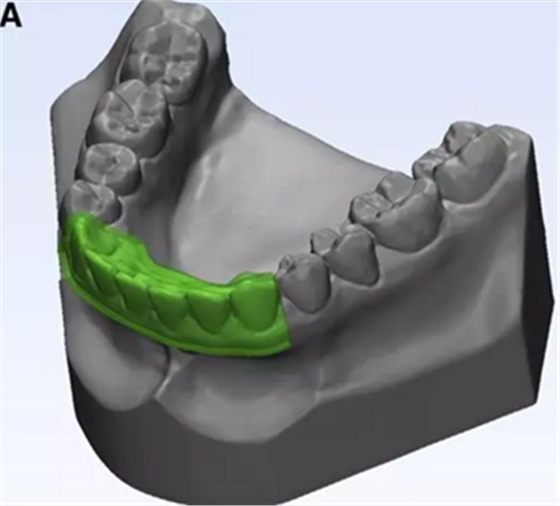

在CBCT成像之前,使用物理下頜石膏模型制造牙合板(圖3中的A)。原始2毫米厚的透明薄板在下頜骨模型上熱成形。然后修剪薄板以覆蓋下頜前牙區(qū),起自牙齦邊緣而終止于雙側(cè)尖牙的遠(yuǎn)中面(圖3,B)。

圖3. A,熱成型薄板的3D模型; B,薄板口內(nèi)試戴。